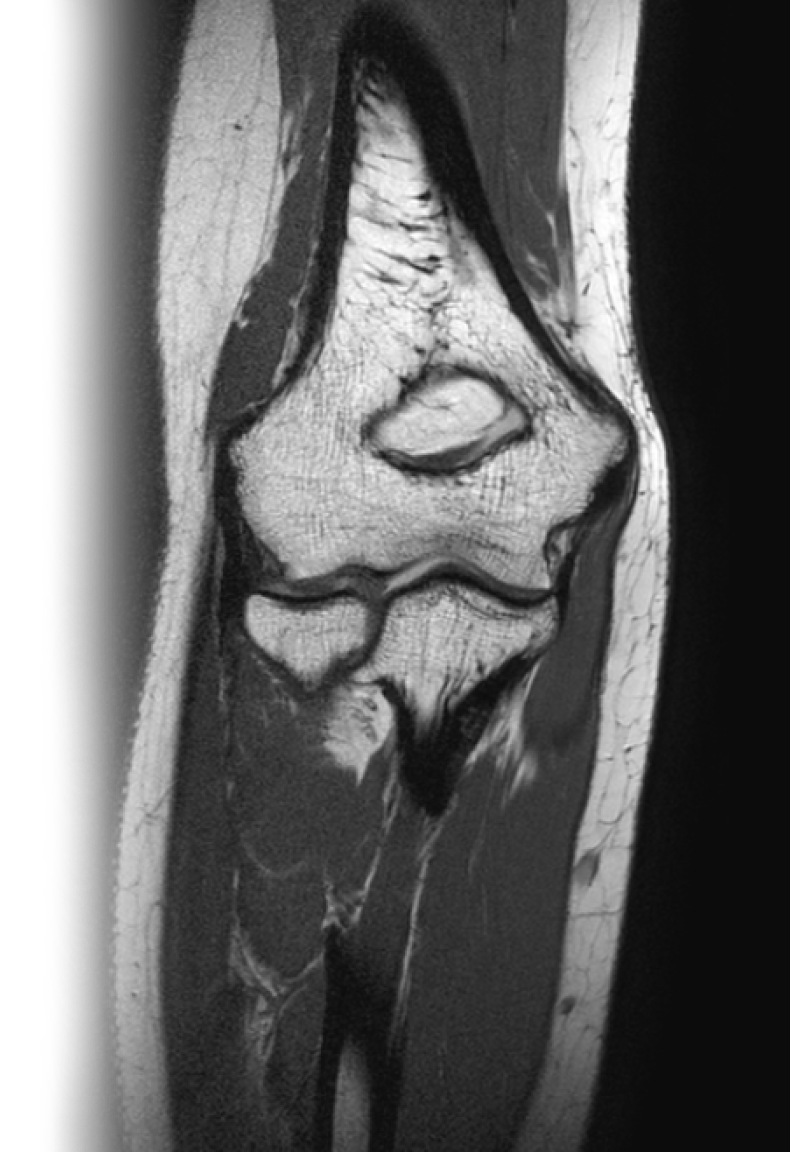

МРТ локтевого сустава

Магнитно-резонансная томография локтевого сустава – важный метод исследования, который позволяет оценить состояние локтевого сустава.